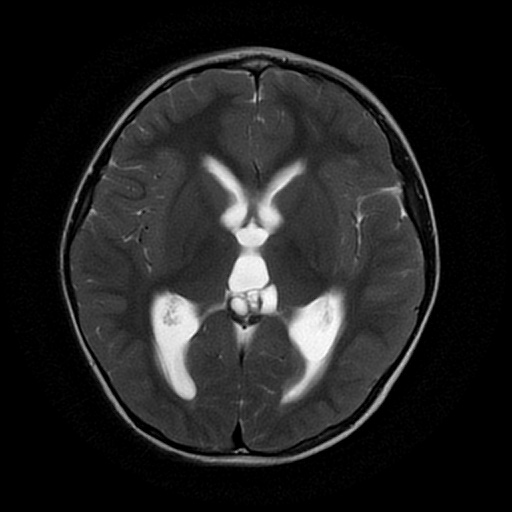

3岁男性患儿,间断头痛两个月入院,头部MR检查结果提示松果体区占位病变并梗阻性脑积水。

头部MR检查T2水平位显示松果体区囊实性占位病变,同时表现侧脑室及三脑室轻度扩张。